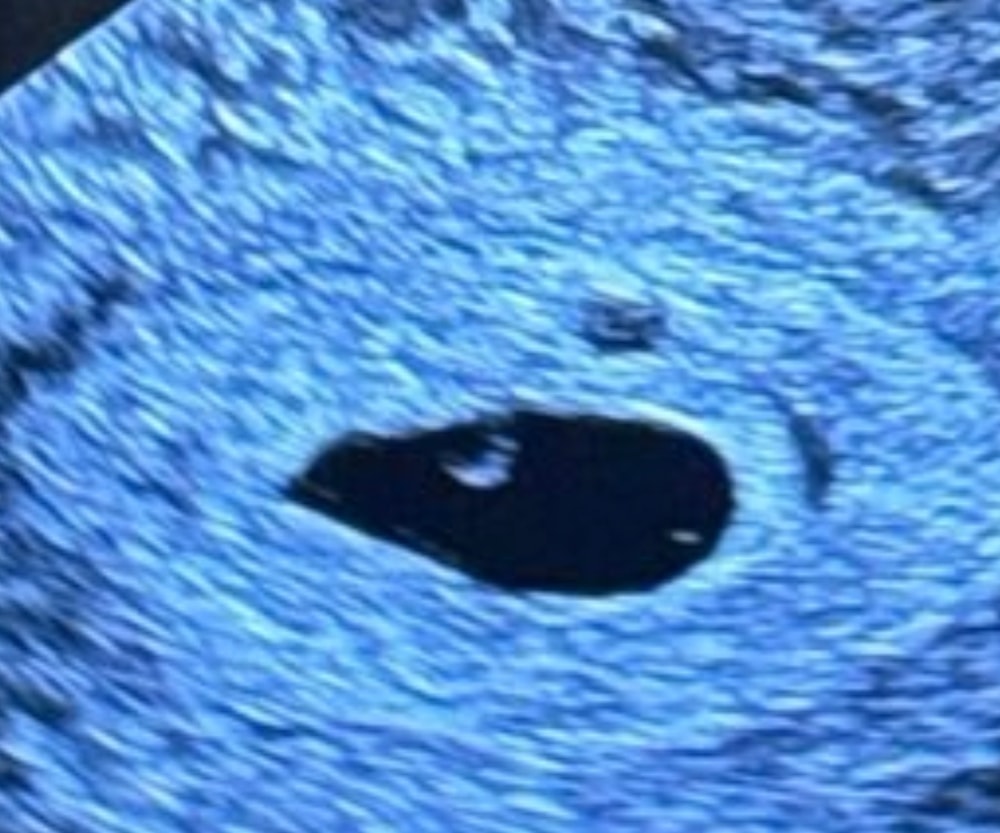

Анна, спасибо, пузырного точно не было Изображение

Кэт Ли, нет) все круто На узи уже нашли человечка и сб 🙏🏻🌸